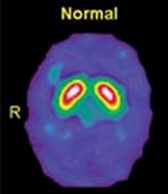

アルツハイマーとパーキンソン病の診断に。Dat scan(ダットスキャン)による認知症検査

dat scan(ダットスキャン)やMIBG検査で認知症を早期診断。早期治療が家族の負担を和らげます。

Datscan(ダットスキャン)だけじゃない!!認知症診断のための核医学検査

新しい認知症の検査:Dat scan(ダットスキャン)検査について